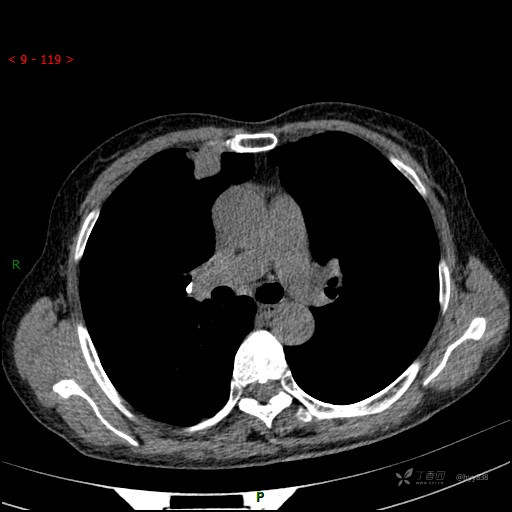

增强动脉期